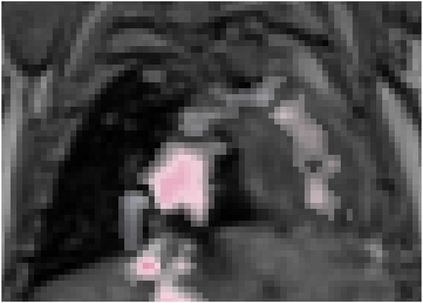

Various imaging modalities allow for time-dependent image reconstructions from measurements where its acquisition also has a time-dependent nature. Magnetic particle imaging (MPI) falls into this class of imaging modalities and it thus also provides a dynamic inverse problem. Without proper consideration of the dynamic behavior, motion artifacts in the reconstruction become an issue. More sophisticated methods need to be developed and applied to the reconstruction of the time-dependent sequences of images. In this context, we investigate the incorporation of motion priors in terms of certain flow-parameter-dependent PDEs in the reconstruction process of time-dependent 3D images in magnetic particle imaging. The present work comprises the method development for a general 3D+time setting for time-dependent linear forward operators, analytical investigation of necessary properties in the MPI forward operator, modeling aspects in dynamic MPI, and extensive numerical experiments on 3D+time imaging including simulated data as well as measurements from a rotation phantom and in-vivo data from a mouse.